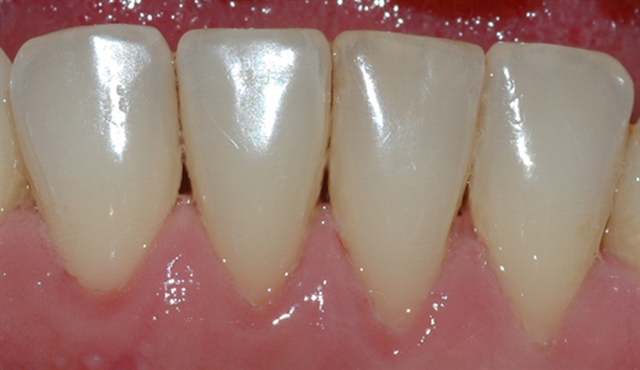

Bildet viser et tannsett med synlig tannsten og misfarging.

• perio stor 6

perio stor 6

Bildet viser et nærbilde av tennene i underkjeven med tannsten og misfarging.